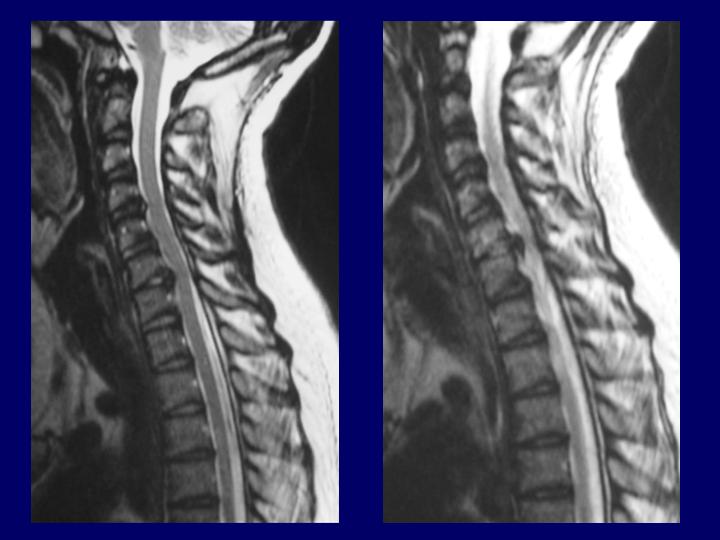

Hernias Discales